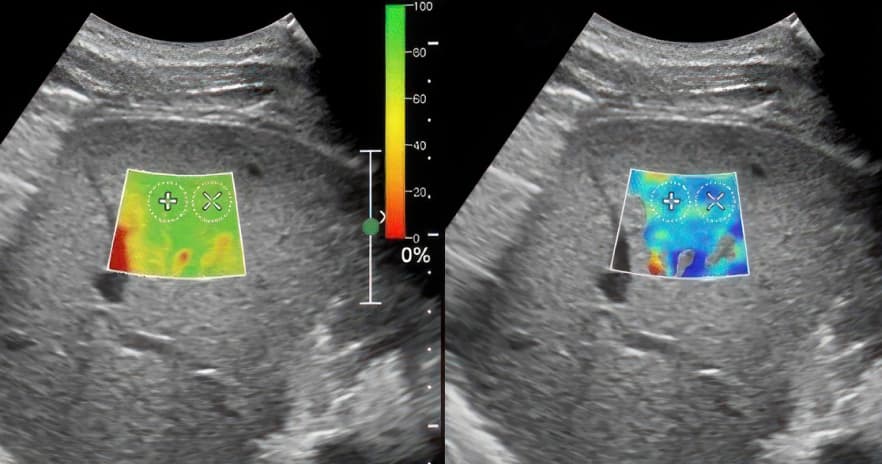

Все відбувається під час звичайного УЗД. Лікар наносить гель, прикладає датчик. Програма автоматично вимірює жорсткість тканини і відображає результат у кольорі: м'які тканини — одним кольором, тверді — іншим. Пацієнт лежить і нічого не відчуває.

Лікар бачить і стандартну УЗД-картину, і еластограму одночасно. Оцінює разом і одразу дає висновок. Жодного болю, жодного опромінення, жодного очікування.

Результат — у кольорах

Еластограма виглядає як кольорова карта тканини. Синій колір позначає високу жорсткість тканин (часто вказує на злоякісне утворення). Зелений колір — тканини середньої жорсткості або здорові тканини. Червоний колір характеризує низьку жорсткість (м'які, еластичні тканини). Це зазвичай вказує на доброякісні утворення. Але інтерпретація завжди за лікарем: колір плюс контекст плюс клінічна картина.